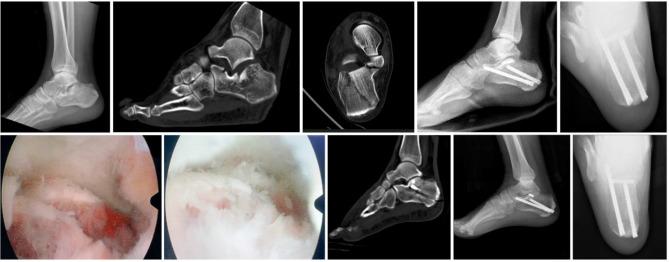

The surgical treatment and management of postoperative soft tissue complications in diabetic patients with displaced calcaneal fractures are still controversial. We aimed to evaluate the short-term efficacy of percutaneous minimally invasive screw fixation in treatment of diabetic patients with Sanders II and III calcaneal fractures under subtalar arthroscopy assisted by preoperative musculoskeletal ultrasonic locating lateral calcaneal branch (LCB) of the sural nerve and calcaneal-talar joint distraction device.

The clinical data of 52 diabetic patients diagnosed with Sanders II or III calcaneal fractures from March 2016 to August 2020 were followed up and analyzed. There were 23 patients of type II and 29 patients of type III, 34 males and 18 females, with a mean age of 61.7 ± 14.5 years (range: 45-72 years). Preoperative musculoskeletal ultrasonography was routinely examined to locate LCB of the sural nerve. During surgery, we performed arthroscopic percutaneous prying reduction screw fixation assisted by medial calcaneal-talar joint distraction. Incision healing, local skin paraesthesia and other conditions were observed regularly at 3 days, 6, 12 months, and the last follow-up after surgery. Also, we measured the length, width, height, Böhler angle, and Gissane angle of the calcaneus on lateral and axial x-rays. Visual analogue pain scale (VAS), American Orthopedic Foot and Ankle Society (AOFAS) score and Maryland score were used to evaluate the efficacy.

52 patients were followed up for 23.7 ± 3.2 months (range: 20-28 months) without incision-related complications. Calcaneal radiographic parameters (length, width, height, Böhler/Gissane angle) were improved after surgery, and the differences were all statistically significant (P<0.05). There was no difference between calcaneal radiographic parameters at 6,12 months and the last follow-up compared with 3 days after surgery without significant loss in overall morphology (P>0.05). Postoperative VAS, AOFAS scores, and Maryland scores were significantly improved compared with those before surgery (P<0.05).

Preoperative ultrasonic locating LCB of the sural nerve and arthroscopic percutaneous minimally invasive screw fixation of Sanders II and III calcaneal fractures with the assistance of calcaneal-talar joint distraction have good short-term efficacy and clinical feasibility in diabetic patients.